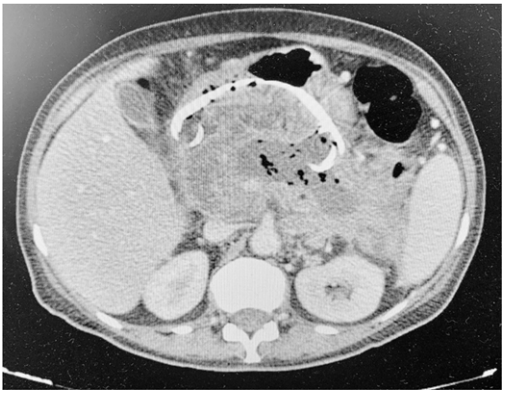

Um paciente, que apresentava pancreatite aguda necrótica complicada há seis semanas, foi submetido a um tratamento.

Com base nesse caso hipotético, é correto afirmar que o exame de controle imediato mostrado acima foi realizado após um tratamento